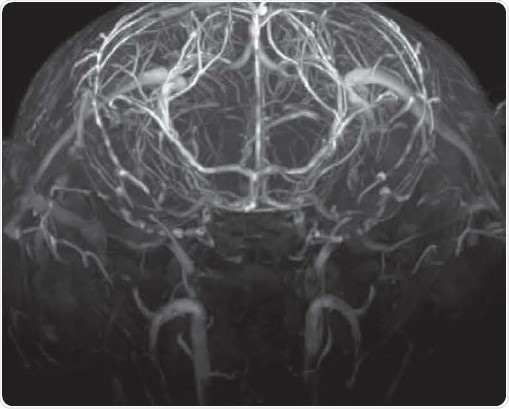

Angiography

Time-of-flight angiography with no contrast agent at high spatial resolution showing excellent contrast enabling the identification of fine vascular structures. Image Credit: Bruker BioSpin Group